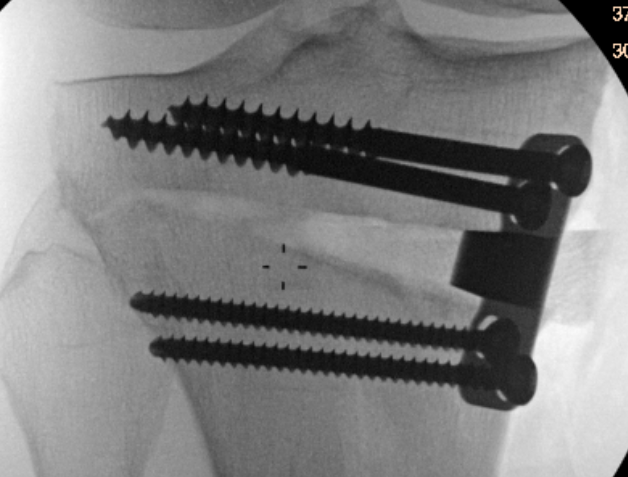

Lateral hinge fracture

Type I hinge fracture

Definition

Extension of the osteotomy into far cortex

May be associated with instability / delayed union / nonunion

Classification lateral hinge fracture after OW HTO

Takeuchi classfication

- type I: extend into lateral cortex above proximal tibio-fibular joint

- type II: extend into lateral cortex below proximal tibio-fibular joint

- type III: extend into lateral tibial plateau